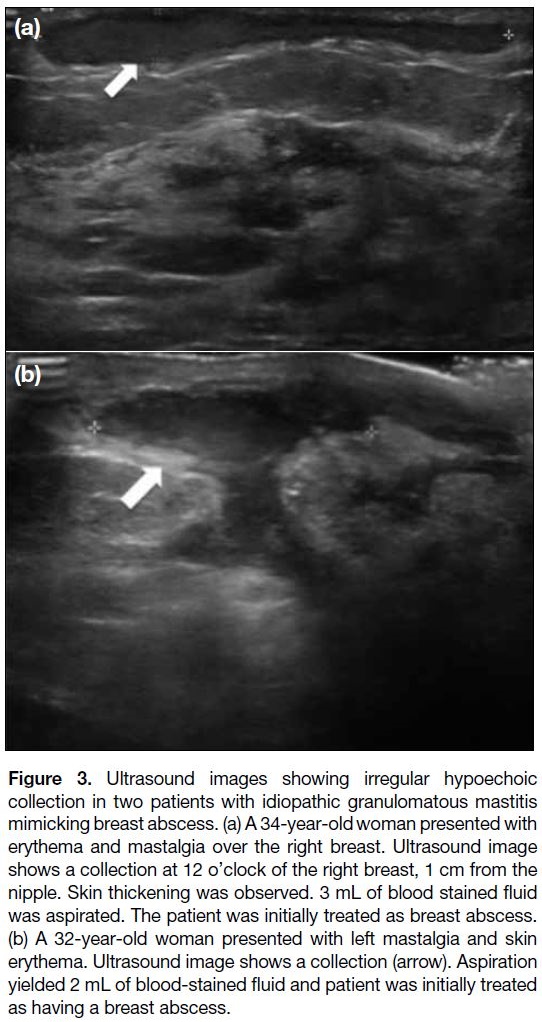

Among the 31 ultrasound examinations, 17 were

(Figure 2), 13 collections (Figure 3) and one parenchymal distortion with no discrete mass. Increased vascularity

was observed in nine of the cases. Associated ultrasound

findings included skin thickening (n = 11), axillary

lymphadenopathy (n = 4), sinus tract formation (n = 4)

(Figure 4) and nipple retraction (n = 2).

Figure 3. Ultrasound images showing irregular hypoechoic

collection in two patients with idiopathic granulomatous mastitis

mimicking breast abscess. (a) A 34-year-old woman presented with

erythema and mastalgia over the right breast. Ultrasound image

shows a collection at 12 o’clock of the right breast, 1 cm from the

nipple. Skin thickening was observed. 3 mL of blood stained fluid

was aspirated. The patient was initially treated as breast abscess.

(b) A 32-year-old woman presented with left mastalgia and skin

erythema. Ultrasound image shows a collection (arrow). Aspiration

yielded 2 mL of blood-stained fluid and patient was initially treated

as having a breast abscess.